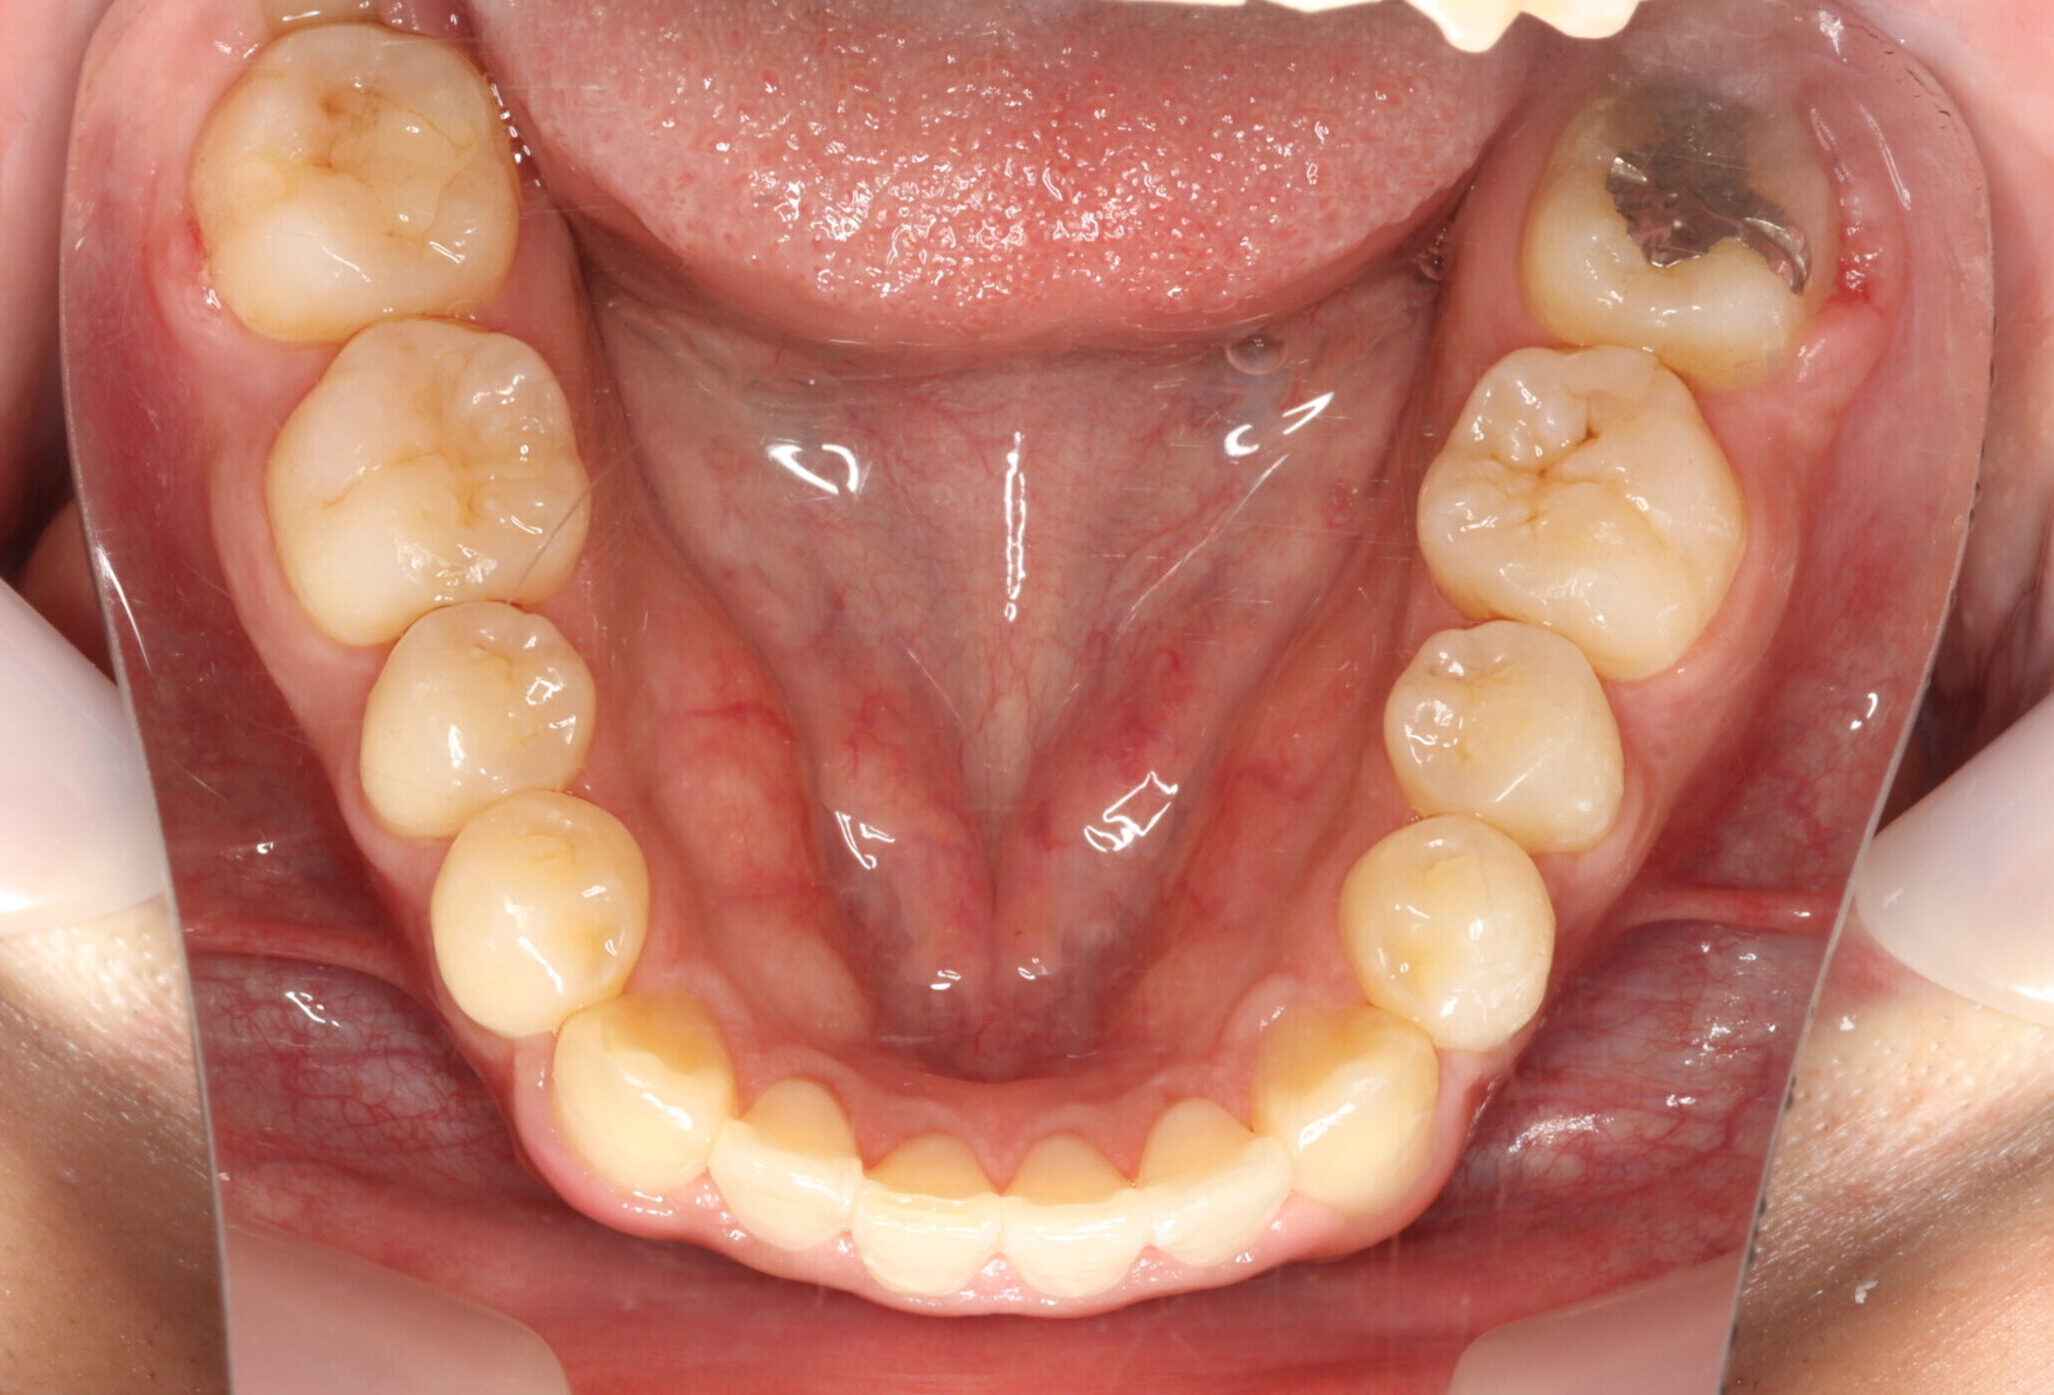

24歳男性 1年11ヵ月

24歳 男性

【主訴】でこぼこ、上下の歯が噛まない

【診断】開咬、叢生(でこぼこ)、上下顎前歯唇側傾斜、舌突出癖

【治療方法】マルチブラケット装置にて排列を行う。咬合の確立のため顎間ゴムを併用し、舌突出癖の改善のため筋機能療法を行う